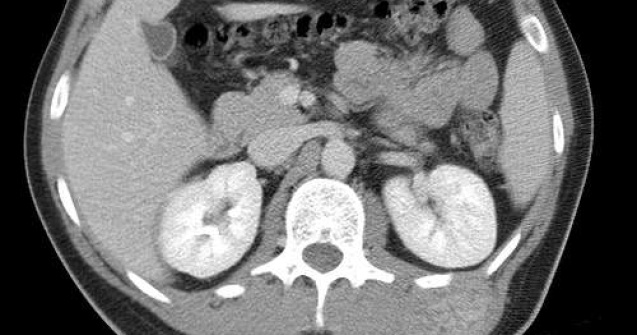

Medicii din Institutul Clinic Fundeni si Spitalul de Urgenta Floreasca au efectuat, din ianuarie 2008 pana in martie 2009, 230 de interventii chirurgicale, folosind sistemul DaVinci, in cadrul unui program pilot pentru Romania de chirurgie robotica